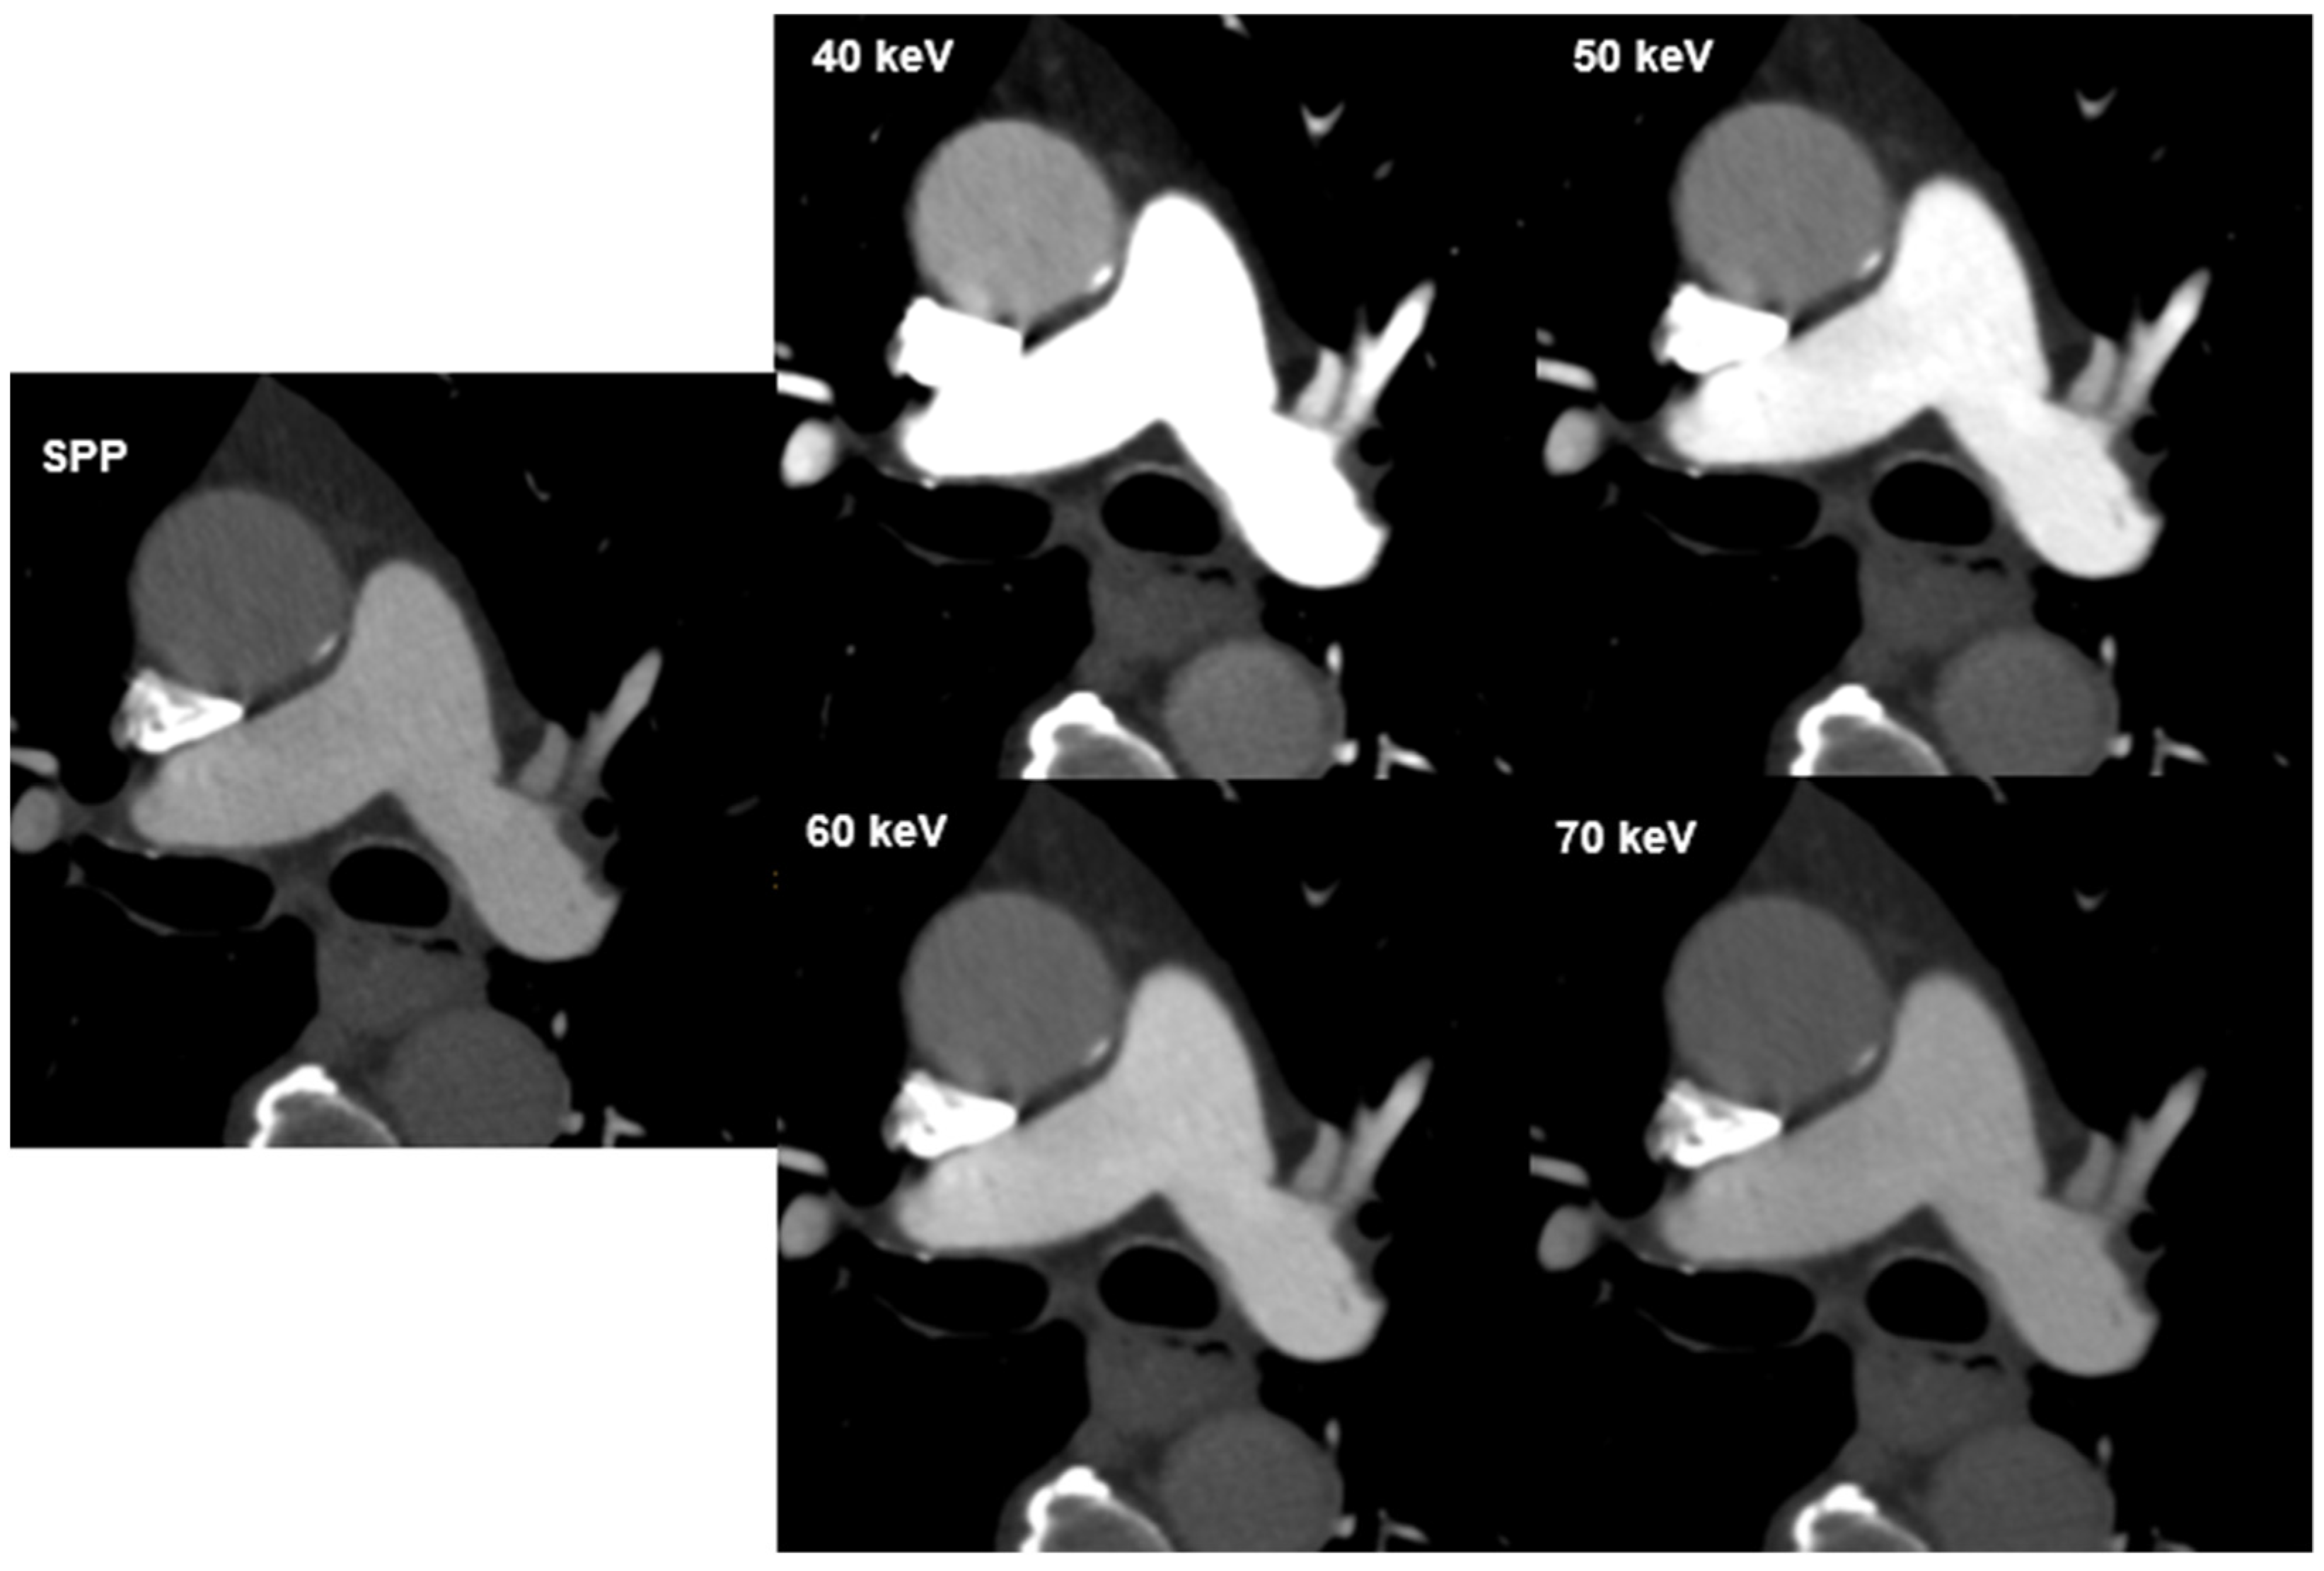

3.3. Subjective Image Quality Evaluation

Overall, inter-reader agreement for subjective image quality was moderate to excellent (Table 4). Excellent agreement was reached in the evaluation of vessel attenuation on VMIs 40–70 keV (k = 0.857–1.000) with total consensus for VMI 40 keV and 50 keV (k = 1.000) and good agreement was reached in the evaluation of vessel sharpness (k = 0.717–0.830). The agreement in image noise evaluation on VMI 40 keV was moderate (k = 0.584), good agreement was achieved for VMIs 50–70 keV (k = 0.644–0.682). Vessel attenuation and vessel sharpness were rated best at 40 keV (both mean 5; range 3–5), while image noise was rated best at 70 keV (mean, 4.6; range 3–5). Subjective scores in the assessment of image noise had positive correlation with VMI energies (r = 0.231, p < 0.001), while there was a negative correlation between VMI energies and vessel attenuation and sharpness (r = −0.557 and r = −0.280; p < 0.001). Hardening artefacts were mainly reported at 40 keV (n = 22; 27.5, followed by 50 keV with n = 10 (12.5%) and 60 keV with n = 1 (1.3%). No hardening artefacts were reported at 70 keV. The visual difference in image quality with regard to image noise and signal is illustrated in Figure 2.

Figure 2. CT images of a 72-year-old male patient at different virtual monoenergetic image (VMI) energies and the multi-energy reconstruction, including all energy spectra (SPP). The visual difference in image quality. Attenuation in the pulmonary artery and aorta depends on the image energy and decreases with increasing VMI energy.